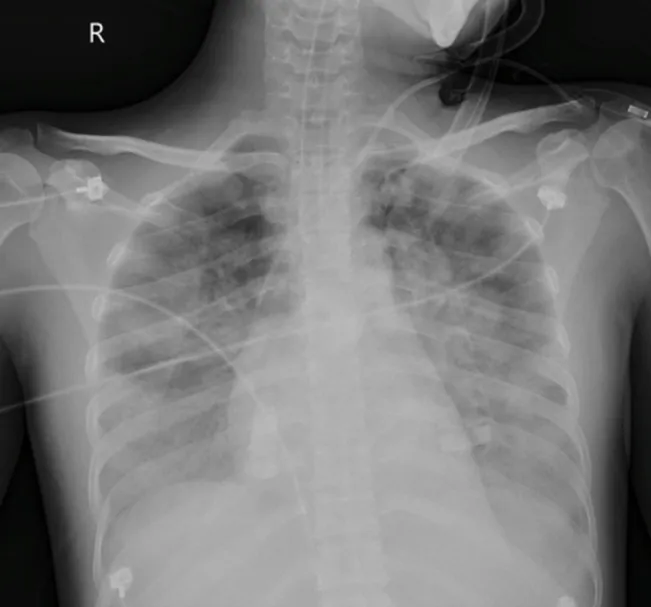

Sau 24 giờ nhập viện, bệnh nhân bị sốc nhiễm khuẩn, được hội chẩn liên viện và chuyển Bệnh viện Nhân dân Gia Định (16-9) để hồi sức chuyên sâu vì tổn thương phổi lan tỏa hai bên (gần 70% thể tích hai phổi).

Hình chụp X-quang phổi của bệnh nhân bị nhiễm "vi khuẩn ăn thịt người". Ảnh: BVCC

Tại khoa Hồi sức tim mạch, bệnh nhân có biểu hiện lâm sàng của hội chứng nguy kịch hô hấp cấp, giảm ôxy máu nặng, nguy cơ phải can thiệp ôxy hóa máu màng ngoài cơ thể. Bệnh nhân được tối ưu hô hấp bằng thông khí bảo vệ phổi và thông khí nằm sấp.